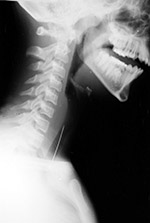

| Turkey bone in the hypopharynx |

Bone in hypopharynx |

Fishbone in hypopharynx |

| 81 year-old man who swallowed a turkey bone (arrows). It is located just posterior to the cricoid cartilage. The bone could not be seen at direct laryngoscopy but was removed at endoscopy. From Hunter, 1994 |

Xeroradiograph of an elderly man with painful swallowing after eating a bowl of "oxtail soup." There is an impacted piece of bone lying anterior to the 7th cervical vertebra. Note the prominently calcified posterior margin of the cricoid bone (arrow). This normal variant should not be mistaken for a foreign body. The impacted bone fragment was removed from the proximal esophagus at endoscopy. From Hunter, 1994 |

68 year-old man with difficulty swallowing after eating fish. A bone (arrow) had perforated the hypopharyngeal wall and was lodged in the soft tissues of the neck. Indirect laryngoscopy was negative, and the bone was removed at surgery after an unsuccessful endoscopy. From Hunter, 1994 |